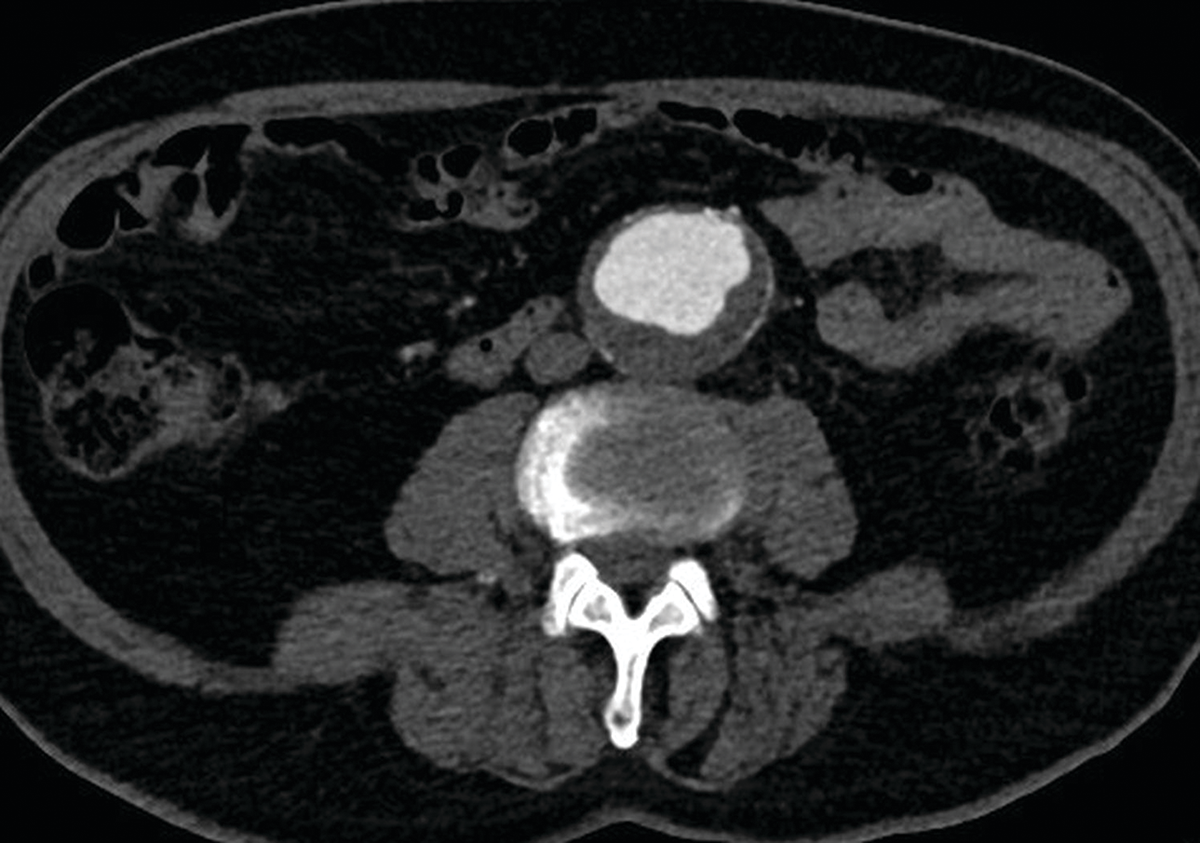

Figure 3

Patient with an infrarenal aortic aneurysm, included in study Group 3.

After intravenous injection of 38 cc of iodinated contrast medium (with 9 cc physiologic saline), the qualitative score was 5 by the two independent observers. The quantitative score was 372 Hounsfield units at the level of the abdominal aortic aneurysm.